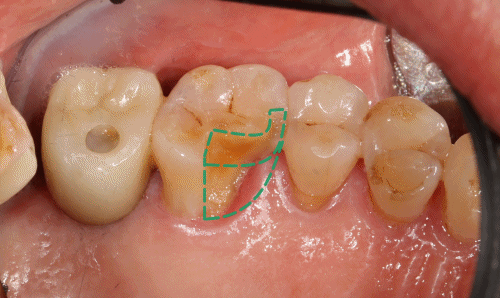

구강 내 모습을 보면

왼쪽 위 첫번째 큰 어금니(26번)이

치수침범이 없는 치아 파절이 확인됩니다.

치수침범이 없다는 것은

신경이 노출되지 않은 상태로

감염 위험이 적고 보존적 치료가

가능하다는 의미입니다.

다만 파절 마진이

치은 연하(잇몸선 아래)까지 이어져 있어

단순 수복만으로는

마진 관리나 장기적 예후 확보가

어려운 상황으로 보입니다.